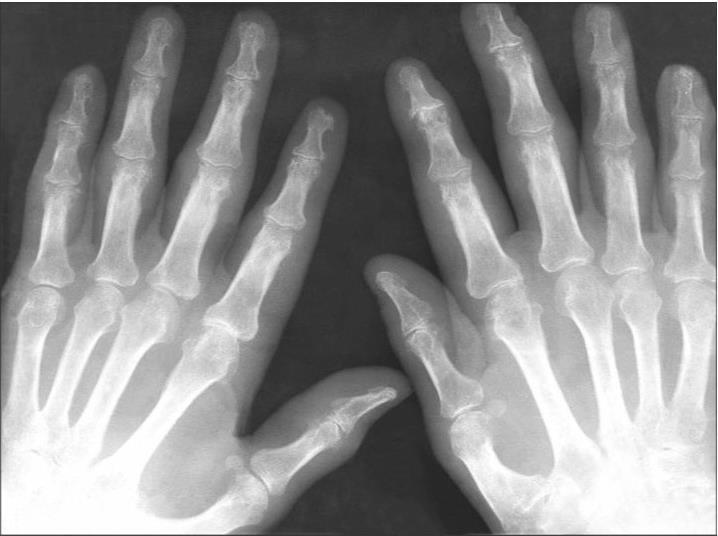

История болезни больного Б., 74 года, сталевара по профессии. В возрасте 69 лет диагностирован рак желудка, удалены 3/4 желудка. В течение последнего года — периодически анемия, постоянное увеличение СОЭ (45–54 мм/ч). В 73 года внезапное развитие левосторонней верхнедолевой пневмонии с массивной инфильтрацией, быстро рассосавшейся после интенсивной антибактериальной терапии. Через две недели, после нормализации процесса в легких, появилось болезненное уплотнение соска левой молочной железы и одновременно боли и отечность суставов обеих кистей. Боли в суставах, довольно интенсивные в начале движения, спустя несколько минут после гимнастики уменьшаются, но полностью не исчезают. При осмотре обращает на себя внимание отечность проксимальных межфаланговых, пястно-фаланговых и лучезапястных суставов. Кожа над суставами цианотична. Умеренные ограничения объема движений в перечисленных суставах из-за болей. Другие суставы внешне не изменены. В области соска левой молочной железы округлое болезненное уплотнение размерами 3 ? 3 см. Увеличены подмышечные лимфоузлы слева. Изменений других органов не обнаружено. В анализе крови — гемоглобин — 112 г/л, лейкоциты — 9,2 (109/л), Э — 2 %, П — 2 %, С — 54 %, Лим. — 37 %, Мои. — 3 %, СОЭ — 44 мм/ч. Ревматоидный фактор в крови отсутствует. На рентгенограммах кистей выражены околосуставной остеопороз, множество мелких краевых деструкций, узур в дистальных, проксимальных межфаланговых, пястно-фаланговых суставах. Отсутствует типичная крупная краевая узурация, свойственная ревматоидному артриту. И, конечно, нетипичная для ревматоидного артрита деструкция в дистальных межфаланговых суставах. Проведенное лечение диклофенаком натрия, димедролом, клофараном, метронидазолом, витаминами С и В эффекта не дало. Сохраняются боли и экссудативные изменения в мелких суставах кистей. Боли в других суставах не присоединились. По-прежнему отсутствуют суточные колебания ритма боли, скованность. Через 3 нед. появились боли и уплотнение в соске правой молочной железы. Учитывая удаление желудка в позднем возрасте, появление инфильтратов в области сосков молочных желез, увеличение лимфоузлов в левой подмышечной впадине, а также стойкость и интенсивность болей только в суставах кистей на фоне анемии, увеличение СОЭ, наличие мелкоочаговой и атипично расположенной деструкции (в дистальных межфаланговых суставах), был поставлен диагноз паранеопластического артрита. Рентгенограмма больного паранеопластическим артритом представлена на рис. 26.

Рис. 26. Рентгенограмма кисти больного паранеопластическим артритом

Виден околосуставной остеопороз, множественные мелкие очаги деструкции в дистальных, проксимальных межфаланговых, в пястно-фаланговых суставах, расположенные не только в субхондральных отделах, но и в головках суставов, диафизах костей